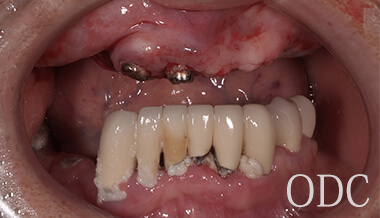

術 前

術前

初診時87歳、男性。上顎は歯周病により残存歯を長期的に機能させることが困難と判断し、全て抜歯。出来る限り早期の咬合機能の回復と審美性の実現が求められ、上顎は「4本のインプラントで失った全ての歯を固定し、手術当日から噛む機能を回復させることが可能」なオールオン4という術式を選択。オールオン4は「治療期間」「経済性」「審美性」「外科的侵襲」などのあらゆる負担を軽減した全く新しいコンセプトの画期的なインプラント治療です。 下顎の欠損部位に対しても、術前の診査診断をしっかり行い合計5本のインプラントを埋入しました。

上部構造

インプラント治療を成功に導く為に必要不可欠な歯科技工。インプラント補綴は、特に技工士の技術が重要となる。オールオン4において、“口の中の見える部分”は全て歯科技工士の仕事なのです。当医院のオールオン4補綴はインプラント補綴で有名なノーベルバイオケア社公認インストラクター 志田和浩氏によるものです。本症例は、1歯1歯プロセラを装着した、オールオン4の上部構造としては最高級のものの一つです。